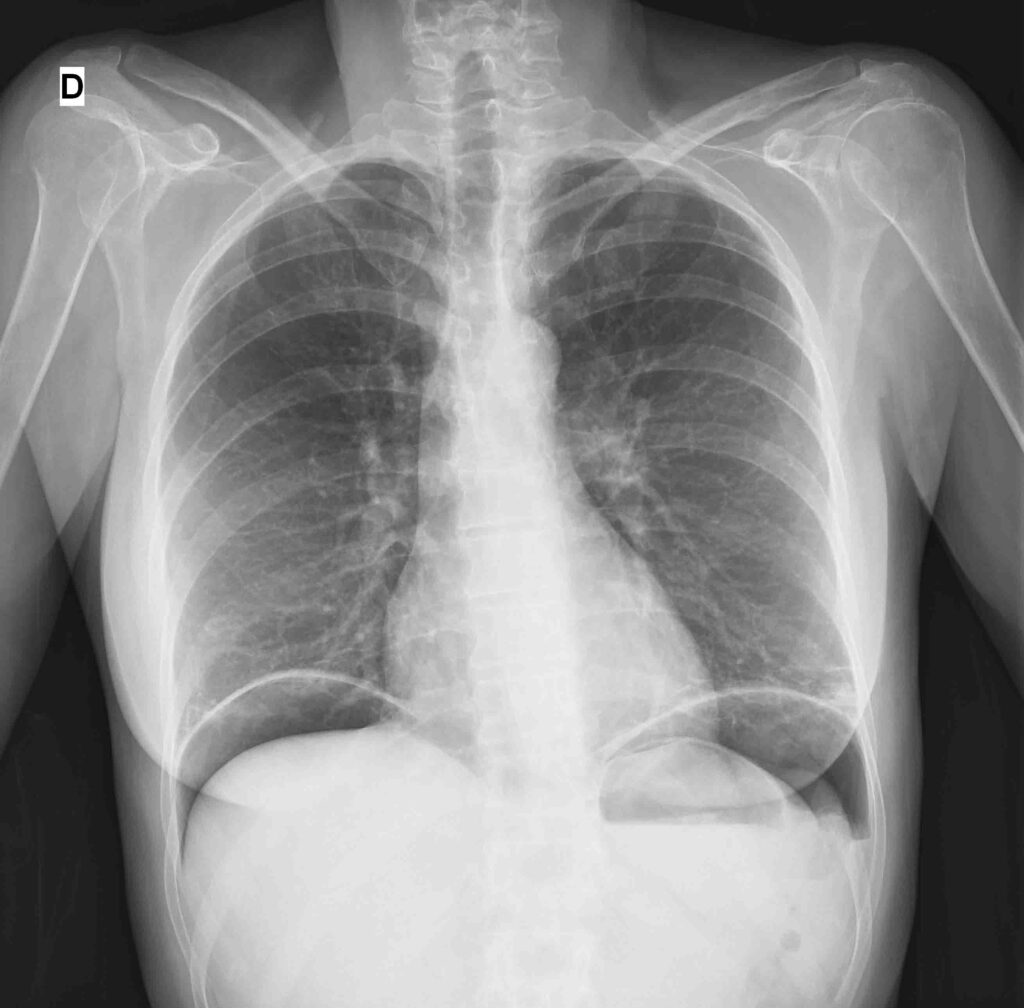

El diagnóstico de la perforación gastrointestinal se sustenta principalmente en las investigaciones radiológicas, que permiten una evaluación rápida y confiable de esta emergencia quirúrgica. En el contexto agudo, la radiografía de tórax en posición erguidaresulta especialmente valiosa, ya que con frecuencia permite identificar la presencia de neumoperitoneo, es decir, aire libre en la cavidad peritoneal, lo que confirma la perforación. Más allá de esto, esta exploración también ofrece información sobre el estado general del paciente, pudiendo revelar condiciones coexistentes como cardiomegalia, neumonía por aspiración o metástasis pulmonares, factores que pueden influir en la planificación del tratamiento y el manejo perioperatorio.

Es relevante tener en cuenta que el neumoperitoneo puede no ser evidente en la radiografía de tórax en posición erguida en aproximadamente el 20–30% de los casos. En situaciones de peritonitis generalizada, cuando la evidencia radiológica es insuficiente o ambigua, el diagnóstico definitivo se establece mediante laparotomía o laparoscopia, procedimientos que permiten una evaluación directa de la cavidad abdominal.